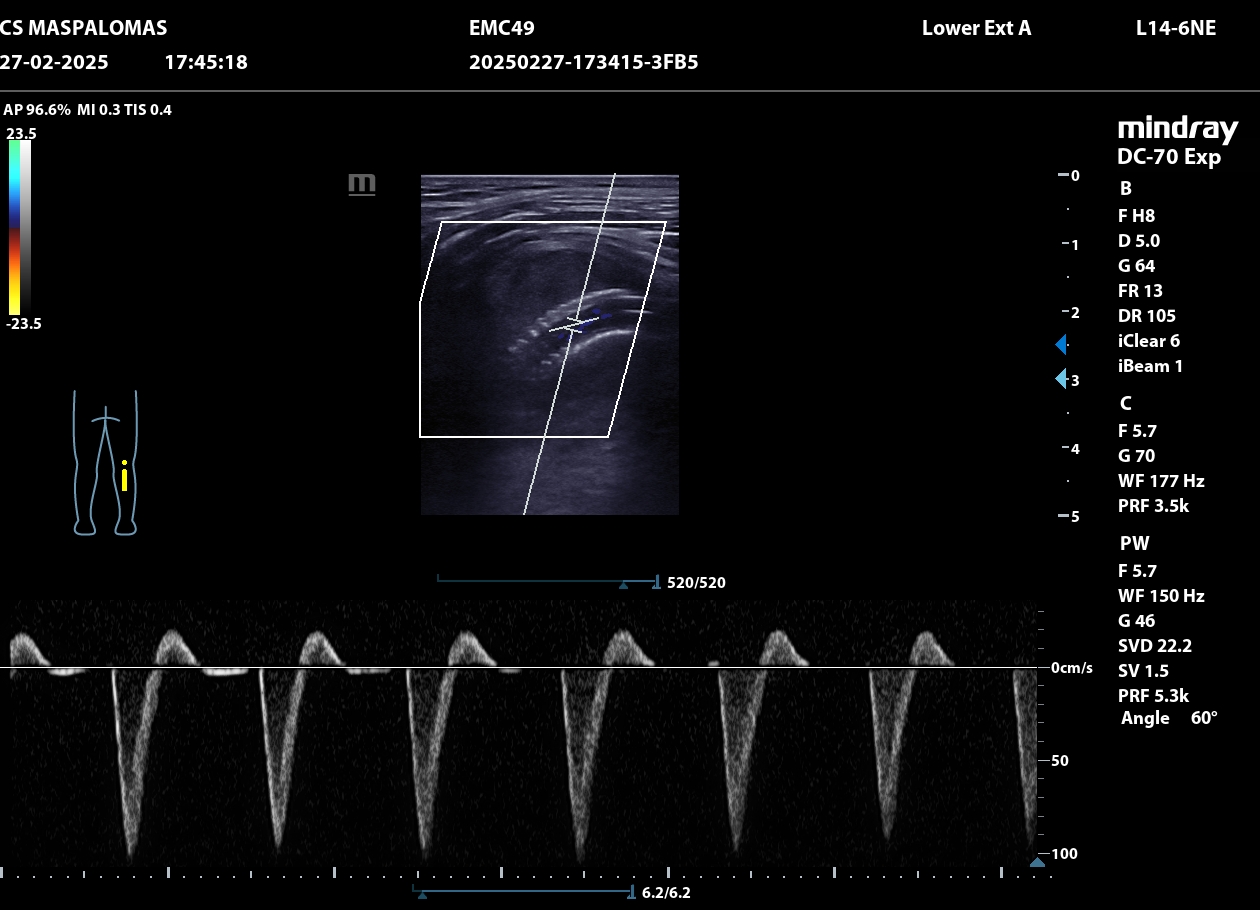

Se realiza ecografía clínica en consulta que revela un aneurisma de la arteria poplítea derecha de 4,66 cm con trombo intraluminal de gran tamaño.

El paciente es derivado a urgencias hospitalarias, se realiza un ECO-Doppler que muestra dilatación de la arteria poplítea derecha de 3 cm con trombo mural, y durante el ingreso en Cirugía Vascular un TAC, confirmando la presencia de un pseudoaneurisma de arteria poplítea derecha de 4,70 x 3,80 cm con trombo mural y salida distal por tres vasos.